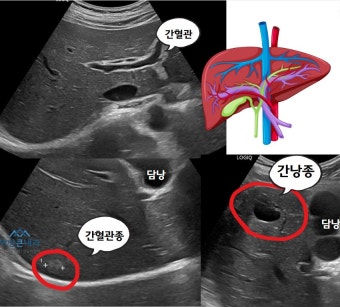

초음파 검사

간낭종 진단에 있어서 가장 흔하고, 간편하며 비용이 저렴한 방법이 복부 초음파 검사입니다. 초음파를 통해 낭종의 위치, 크기, 내부 구조 등을 확인할 수 있으며, 낭종이 단순한 형태인지 혹은 복잡한 형태인지 구분하는 데 유용합니다.

단순 낭종의 경우, 초음파상에서 경계가 매끄럽고 내부가 맑은 액체로 보이며, 음향 투과도가 좋습니다. 반면, 기생충성 낭종이나 출혈성 낭종은 내부에 격막이나 혼탁한 내용물이 보일 수 있어 단순 낭종과는 구별됩니다.

또한 초음파는 실시간으로 진행 가능하며, 검사 중 복통 부위를 눌러 통증 유발 여부도 확인할 수 있어, 임상적인 참고 자료로 매우 유용합니다.